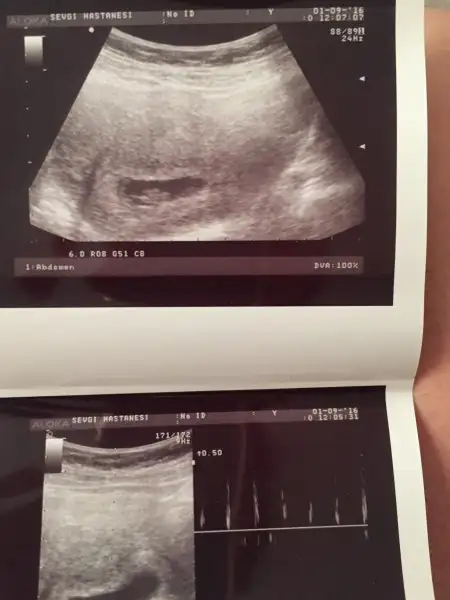

Siz kaç haftalıksınız?Bende öğrenemedim yine

Ayy bu resimi buldum şimdi bakkKaç haftalık simdi

Ayy bu resimi buldum şimdi bakk

Kaç haftalık simdi

Bi yorum da benim minige rica edebilir miyiz? 7+3 batın usg. Tesekkurler:)Eki Görüntüle 1879196

Kese büyük ise kız küçük ise erkek ben geçmiş yorumlarina bakmişim.. doğru mu bilmiyorum. bazilarin tam tersi olabiliyo kişiden kişiye degişiyor.Eki Görüntüle 1879943 Kızlar bilen varsa yorum yapsın bari dundendir bekliyorum son adet tarihine göre 10 + 2 iki gün önce doktora gittim ultrasonda 11 haftalık çıktı

öle oluyormuş fasulye gibiyse erkek yuvarlak ise kızmiş:)Havalianne__ burda benim bebeğim 8+5 haftalık. Kese yuvarlaksa kız fasulye gibiyse erkek miydi. Benimki tam yuvarlak da değil tam fasulyede değil sanki. Ona göre bi bakar mısın